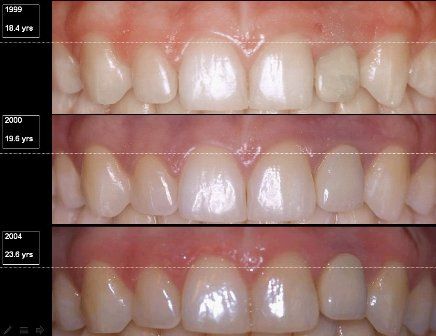

İMPLANT DİŞLERİ DOĞAL GÖRÜNÜR MÜ? İmplant kemik ve dişeti altında yerleşmektedir. Bu sebeple üstüne yapılan dişle herhangi bir uyumsuzluk söz konusu olmamaktadır. Özellikle son dönemlerde gelişen zirkon üst yapılar sayesinde ön bölge estetiğinde bile tam bir uyum sağlanmaktadır.